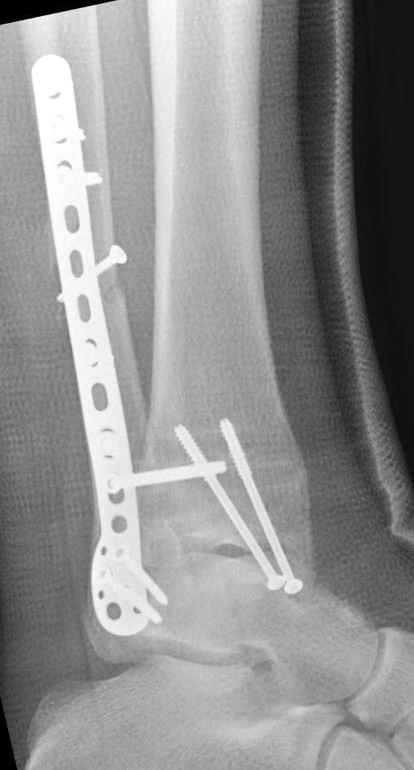

Если до сих ничего не сделано, с артродезом сустава в данный момент я бы повременил, на выставленных январских снимках хорошо сохранившийся сустав, а в "мортиз" (трехчетвертной) и на боковых снимках не менее 5 мм укорочение малоберцовой кости. Косые переломы лучше фиксировать пластинами, как то мы разбирали случай, где было отмечено, что это закон "таранная кость всегда следует за малоберцовой".

В данном случаи я бы уговорил больного на реконструкцию, для этого после удаления шурупов, спереди очистить от рубцов синдесмоз, несросшуюся наружную лодыжку - остеотомия по линии перелома и компрессирующий (lagging technique) кортикальный шуруп 3.5 мм по поперечнику остеотомии. Следующий этап - восстановление длины малоберцовой за счет удлинения, сделать поперечную остеотомию где-то на уровне сантиметр выше вашего синдесмозного шурупа, наложить длинную пластинку, прикрепить пластину за дистальный конец двумя или тремя шурупами; сохраняя контакт пластины с костью, имеющимся

compression&tension device AO system (при отсутствии любой lamina spreader подойдет, создать дистанцию между пластиной и шурупом, проведенным проксимальнее пластины) толкая проксимальный отдел пластины, низвести пластину, мортиз рентгенограмма подскажет на сколько. Если заранее сделать предоперационный план (ренгенограмма другой стороны), тогда точно можно определить, на сколько вам необходимо сделать поперечную остеотомию малоберцовой кости, для закрытия создавшегося дефекта.

Убедившись, что желаемая длина восстановлена, окончательная фиксация пластины, при этом через пластину пару 3.5 мм шурупов на синдесмоз, предпочтительно в четыре кортекса и оставить на 3 мм длиннее, если под нагрузкой синдесмотический шуруп сломается, сломанный конец легче удалить с медиальной стороны.

Медиальная сторона не в нагрузочной зоне, и там большая дыра - если есть 2.7 мм шурупы, или пару спиц в ваших условиях или методика Лазарева. Необходимо уделить внимание к мягким тканям, обнажается кость с латеральной стороны и у места где проводится остеотомия.

Недавний случай, больной 56 лет получил политравму в Англии, после переведен в США, где его успешно лечил местный ортопед, огромная статья в газете об успешной операции, своеобразный пиар, из-за того, что больной был американский пожарник на пенсии, и за его переезд было заплачено международным пожарным союзом, короче по другим показаниям перевели больного в наш университетский госпиталь.

После 5-6 недели после травмы сделана повторная операция, обошлись без удлинения малоберцовой.